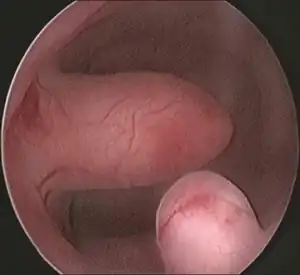

| Endometrial polyp at hysteroscopy | |

Hysteroscopy

Other tests include hysteroscopy.[2]

Pedunculated endometrial polyp

Pedunculated endometrial polyp Sessile endometrial polyp

Sessile endometrial polyp Bleeding and endometrial polyp

Bleeding and endometrial polyp Multiple endometrial polyps

Multiple endometrial polyps Multiple endometrial polyp

Multiple endometrial polyp